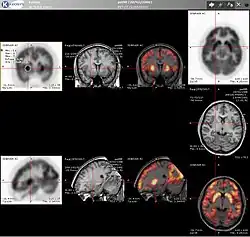

F-FDG (fluorodeoxyglucose). The normal brain and kidneys are labeled, and radioactive urine from breakdown of the FDG is seen in the bladder. In addition, a large metastatic tumor mass from colon cancer is seen in the liver.

PET scanning with the radiotracer [18F]fluorodeoxyglucose (FDG) is widely used in clinical oncology. FDG is a glucose analog that is taken up by glucose-using cells and phosphorylated by hexokinase (whose mitochondrial form is significantly elevated in rapidly growing malignant tumors).[4] Metabolic trapping of the radioactive glucose molecule allows the PET scan to be utilized. The concentrations of imaged FDG tracer indicate tissue metabolic activity as it corresponds to the regional glucose uptake. FDG is used to explore the possibility of cancer spreading to other body sites (cancer metastasis). These FDG PET scans for detecting cancer metastasis are the most common in standard medical care (representing 90% of current scans). The same tracer may also be used for the diagnosis of types of dementia. Less often, other radioactive tracers, usually but not always labelled with fluorine-18 (18F), are used to image the tissue concentration of different kinds of molecules of interest inside the body.

A typical dose of FDG used in an oncological scan has an effective radiation dose of 7.6 mSv.[5] Because the hydroxy group that is replaced by fluorine-18 to generate FDG is required for the next step in glucose metabolism in all cells, no further reactions occur in FDG. Furthermore, most tissues (with the notable exception of liver and kidneys) cannot remove the phosphate added by hexokinase. This means that FDG will remain trapped in any cell that takes it up until it decays, since phosphorylated sugars, due to their ionic charge, cannot exit from the cell. This results in intense radiolabeling of tissues with high glucose uptake, such as the normal brain, liver, kidneys, and most cancers, which have a higher glucose uptake than most normal tissue due to the Warburg effect. As a result, FDG-PET can be used for diagnosis, staging, and monitoring treatment of cancers, particularly in Hodgkin lymphoma,[6] non-Hodgkin lymphoma,[7] and lung cancer.[8][9][10]